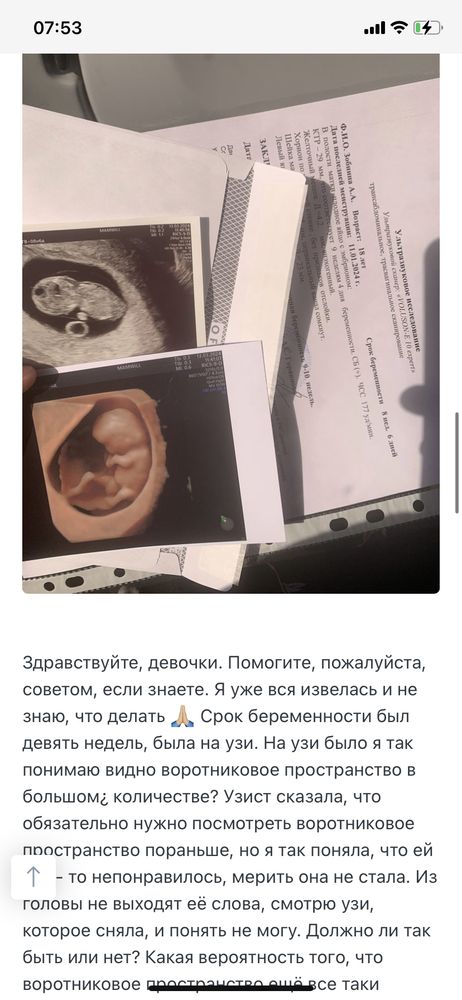

Девочки, доброе утро.. Приложу описание своей ситуации по узи в 9 -то неделек (первые пять фото). Ходила на узи в 9,5 недель (шестое фото) Всё таки есть расширение воротникового пространства? Хожу в платную клинику с самого начала беременности. Попросила её измерить все таки, она померила, но там, где маленькое воротниковое пространство и сказала 1,5, но можно было замерить в другом месте, где оно больше. Вроде в конце она померила большой замер и ничего не сказала мне, а я обратила на это внимание 😢 Я её спросила несколько раз, она сказала, что все хорошо, но мне кажется, что она меня так просто успокаивает..